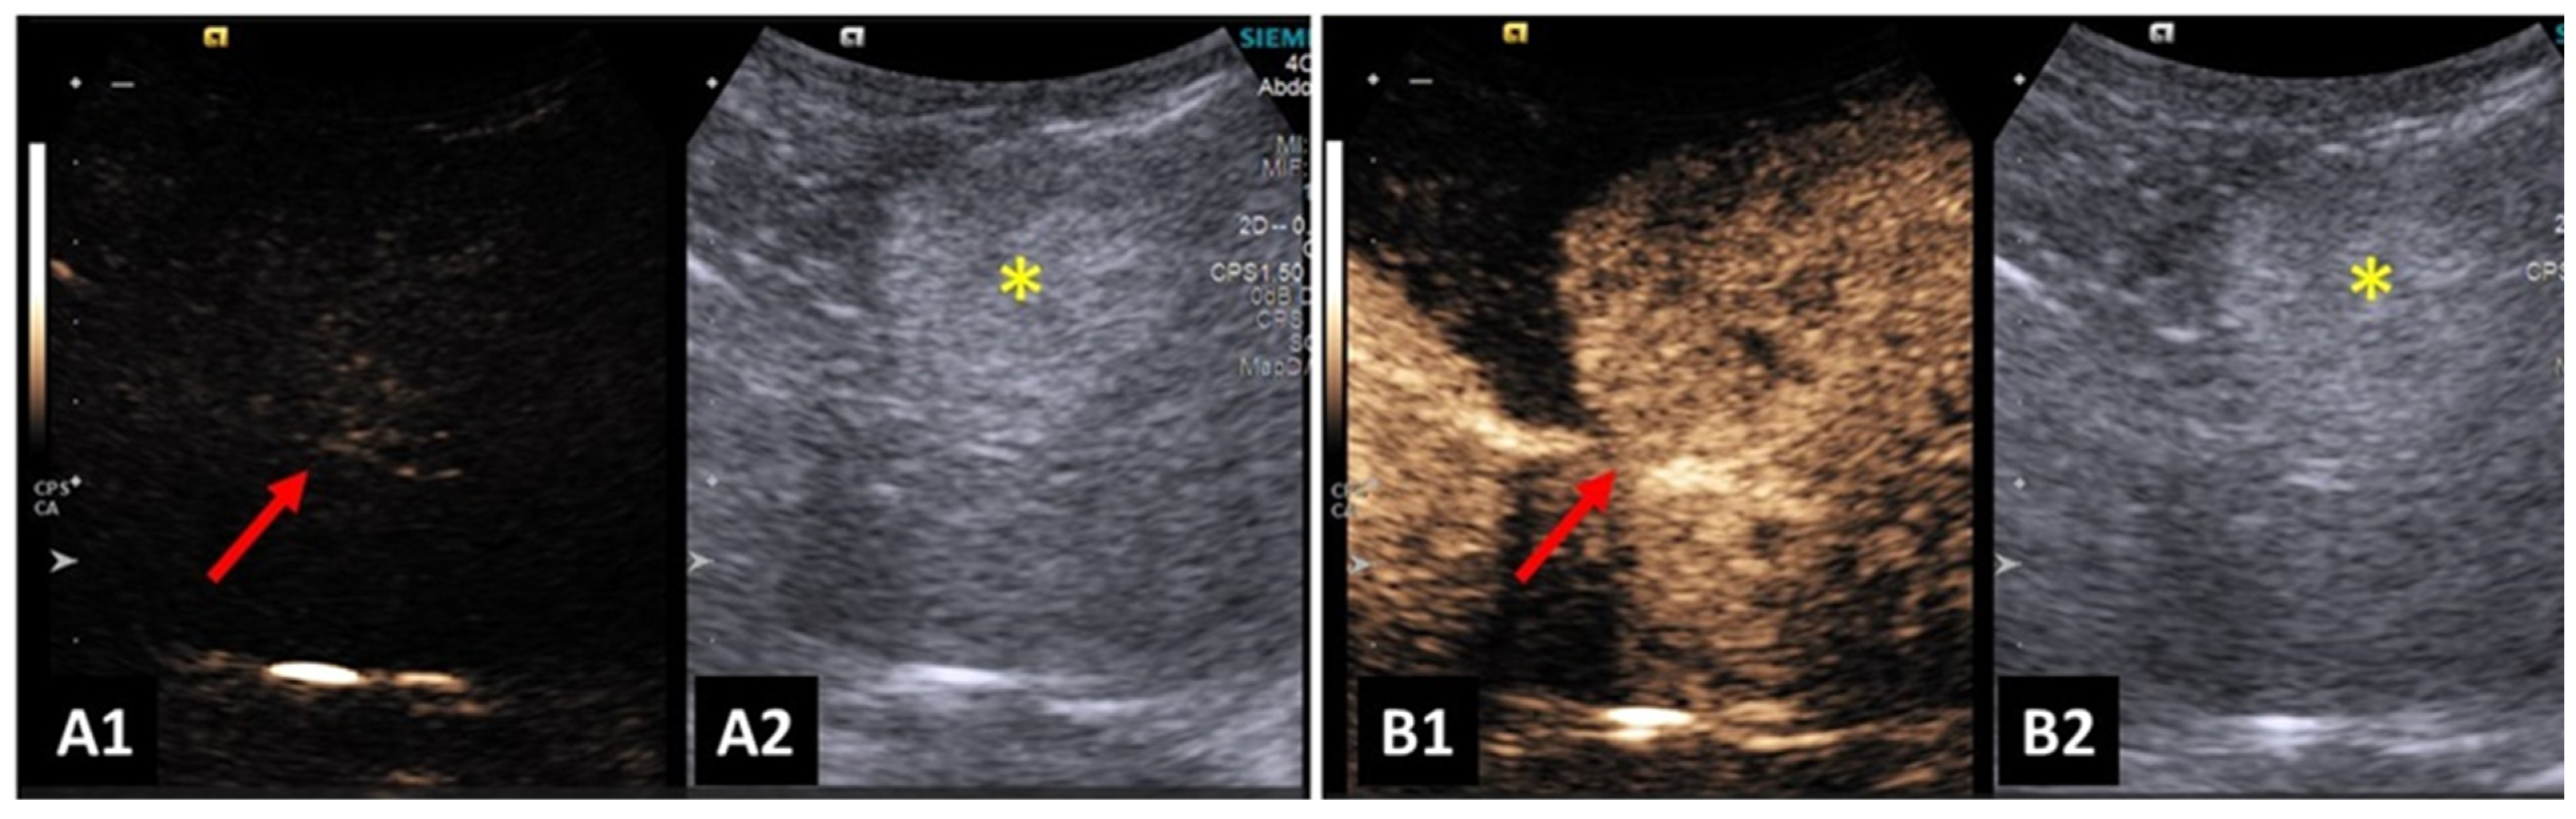

4.7. Liver and Biliary System

- Banzato, T.; Rubini, G.; Orlandi, R.; Bargellini, P.; Bonsembiante, F.; Zotti, A. Contrast-enhanced ultrasound features of hepatocellular carcinoma in dogs. Vet. Rec. 2020, 186, 187. [Google Scholar] [CrossRef] [PubMed]

- Burti, S.; Zotti, A.; Rubini, G.; Orlandi, R.; Bargellini, P.; Bonsembiante, F.; Banzato, T. Contrast-enhanced ultrasound features of malignant focal hepatic masses in dogs. Sci. Rep. 2020, 10, 6076. [Google Scholar] [CrossRef] [PubMed]

- O’Brien, R.T.; Iani, M.; Matheson, J.; Delaney, F.; Young, K. Contrast harmonic ultrasound of spontaneous liver nodules in 32 dogs. Vet. Radiol. Ultrasound 2004, 45, 547–553. [Google Scholar] [CrossRef]

- Nakamura, K.; Takagi, S.; Sasaki, N.; Kumara, W.R.B.; Murakami, M.; Ohta, H.; Yamasaki, M.; Takiguchi, M. Contrast-enhanced ultrasonography for characterization of canine focal liver lesions. Vet. Radiol. Ultrasound 2010, 51, 79–85. [Google Scholar] [CrossRef] [PubMed]